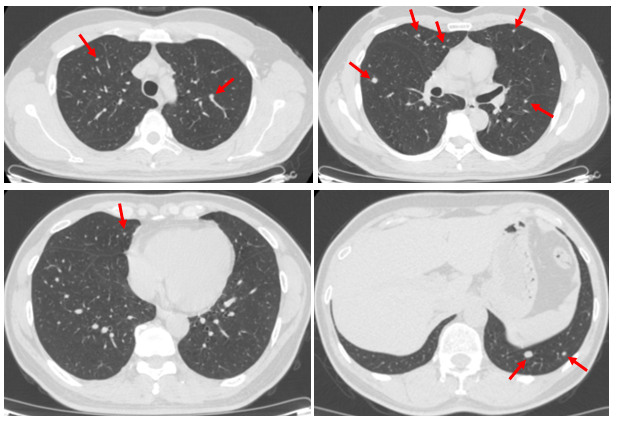

Hình ảnh Cắt lớp vi tính lồng ngực trước điều trị (6/2022):

Hình 1: Nhu mô hai phổi có nhiều nốt mờ, bờ đều ranh giới rõ, nốt lớn đường kính 14mm, một số nốt có vôi hóa bên trong (mũi tên đỏ).